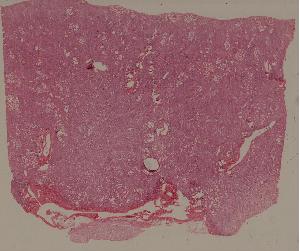

49.梅毒性主动脉炎

50.大叶性肺炎

51.肺肉质变

52.小叶性肺炎

57.肺癌

59.慢性萎缩性胃炎

60.胃溃疡

61.胃腺癌(胃粘液腺癌)

62.急性普通型病毒性肝炎

63.慢性活动性肝炎

64.急性重型病毒性肝炎

65.亚急性重型病毒性肝炎

66.活动性结节性肝硬化

67.非活动性结节性肝硬化

68.胆汁性肝硬化

69.肝细胞性肝癌

72.膜性肾小球肾炎

73.急性肾小球肾炎

74.新月体性肾炎

75.慢性硬化性肾小球肾炎